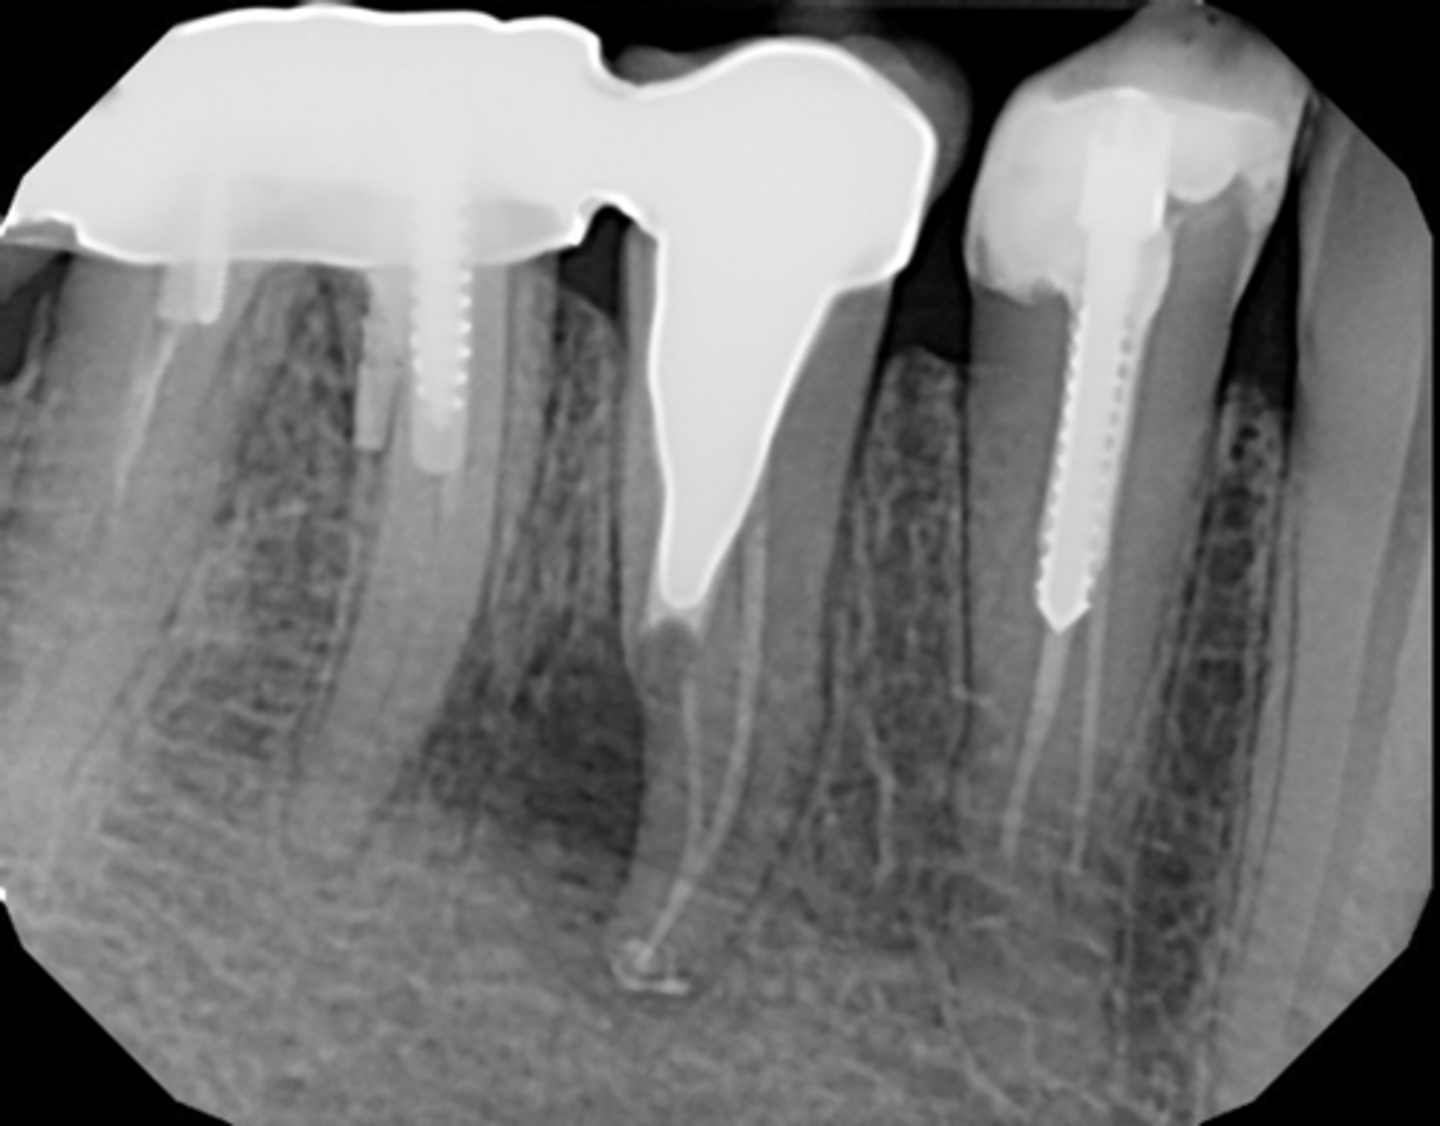

Infected silver point (Retreatment should be attempted first)

What is the cause of this apical radiolucency?